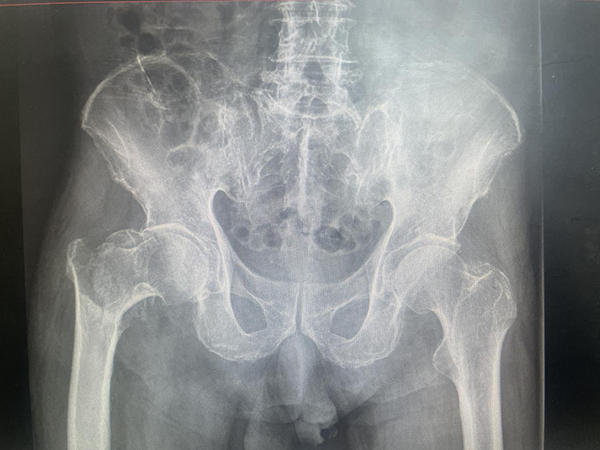

惠正廣團(tuán)隊(duì)為陳大爺制定了詳細(xì)而周密的中西醫(yī)結(jié)合的多學(xué)科聯(lián)合(MDT)診療方案,在麻醉科及手術(shù)室護(hù)理團(tuán)隊(duì)的精心配合下,手術(shù)非常成功。術(shù)后經(jīng)功能康復(fù),以及中醫(yī)藥特色技術(shù)的綜合治療,陳大爺終于可以下床活動(dòng)了。

●(術(shù)后X線片)